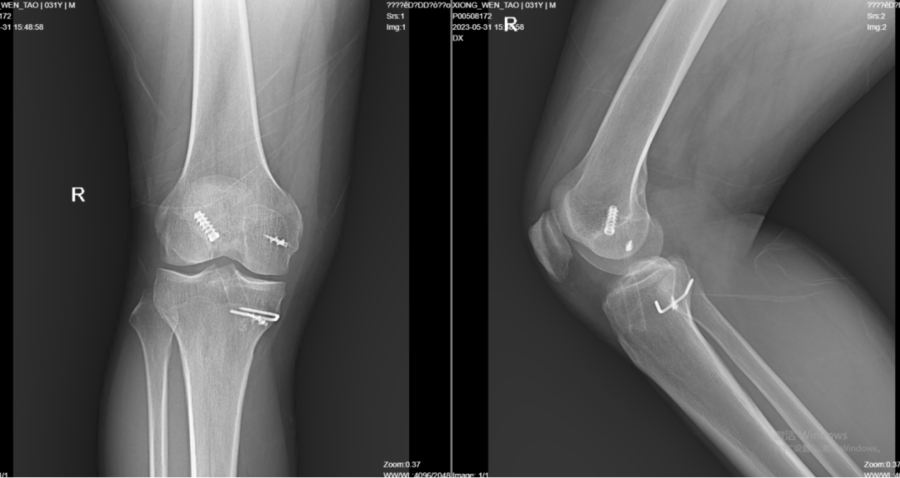

6月2日,高玉镭主任为患者实施“股薄肌、半腱肌、腓骨长肌取腱术+关节镜下右膝前交叉韧带重建翻修术+半月板缝合术”,术中所见:前交叉韧带部分断裂、松弛,韧带内淤血,外侧半月板后角撕裂。高玉镭主任介绍说:“手术过程中,刨削器刨除关节内积血,彻底止血。给予缝合外侧半月板后角。然后,于胫骨结节内侧取出两条肌腱,于右踝关节外侧切口内取1/3腓骨长肌肌腱,并在工作台上对其预处理,接下来才是相关重建流程。整个手术过程比较复杂,但彻底解决了手术后各种并发症隐患。”